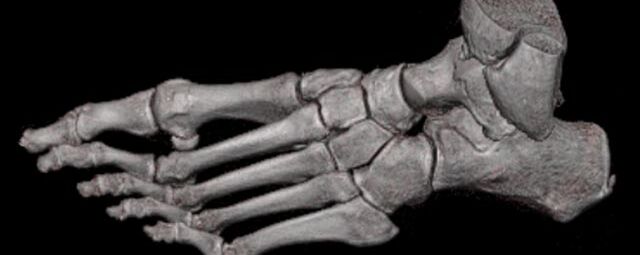

Extremitäten

• bei komplizierten Frakturen z. B. in der Nähe von Gelenken oder im Bereich der Handwurzel und Fußwurzel

• besonders hochauflösende, strahlendosissparende Darstellung aller Skelettstrukturen